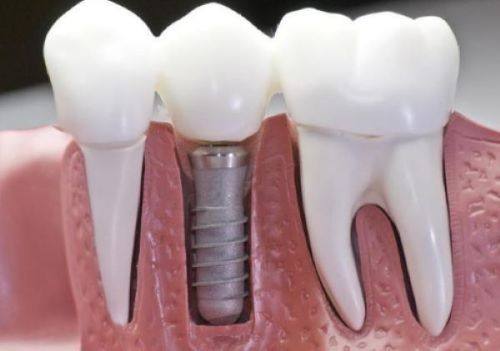

口腔种植的费用主要由种植体、牙冠和医疗服务这三个部分组成。其中,医疗服务部分在种植牙整体费用中所占的比重相对较高。近期国内范围内的登记调查初步结果显示,以各省份国有医疗机构单颗常规种植为例,医疗服务部分的平均费用超过了6000元,有些省市甚至超过了9000元。这也是导致种牙费用居高不下的一个重要原因。过高的价格让特别多患者只能对种植牙望而却步,而现在政策的实施有望改变这一现状,实现种植牙价格大幅下降,让更多人能够负担得起种牙费用。